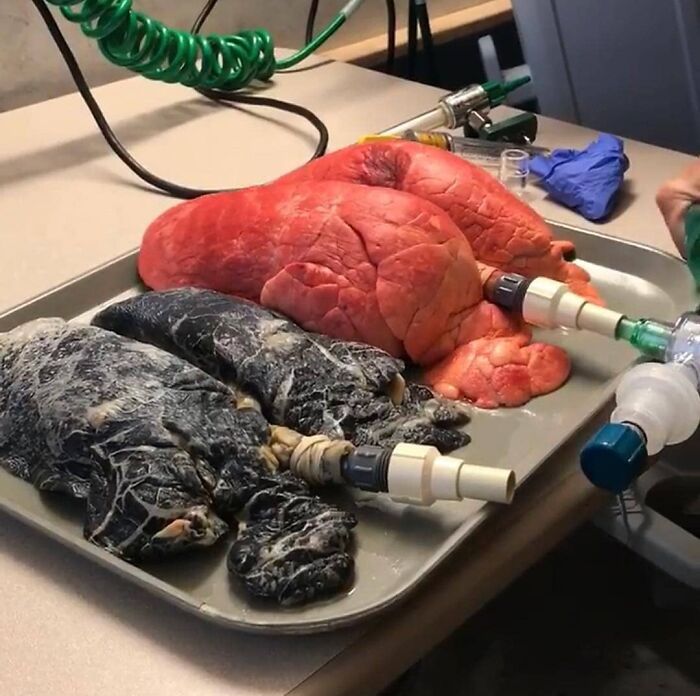

#9 Grafické porovnanie zdravých pľúc a pľúc silného fajčiara